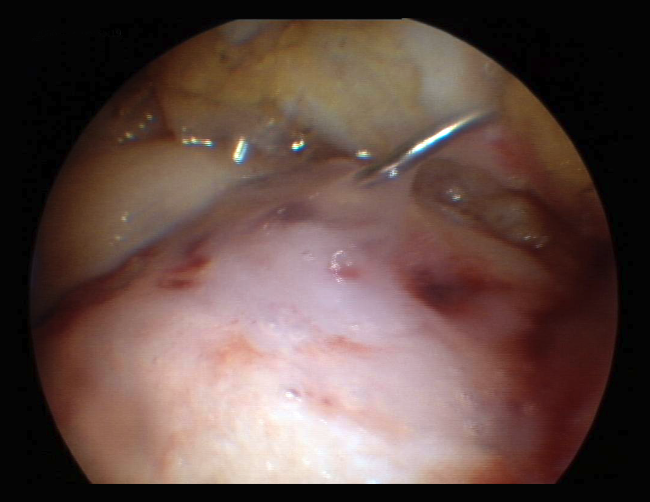

Despite these undeniable and proven benefits, however, chitosan is very unstable, and the elaboration of products containing it therefore poses major challenges. A very interesting property of this biopolymer is the fact that when in liquid state, it transforms into a semisolid gel upon reaching human body temperature(24). This discovery was very useful in searching for a formulation that may be injected into a joint such as the knee in the course of an arthroscopic procedure, with solidification in situ in only a few minutes. The decision was therefore made to use it as a coadjuvant in BMS procedures. In 2005, the Canadian company BioSyntech – posteriorly Piramal Healthcare (Canada), Bio-Orthopedics Division – started an international, randomized, comparative clinical study contrasting microfractures alone with microfracture plus versus their product, BST-CarGel® (currently Smith & Nephew, Wartford, UK). The results after both 12 months and at 5 years of follow-up evidenced sustained superiority over time of BST-CarGel® versus microfractures alone. This superiority was reflected by both the greater hyaline quality and quantity of the formed tissue, as measured objectively using quantitative magnetic resonance imaging (MRI) techniques(25,26)(Figure 4).

Figure 4. A: extensive chondral lesion of the internal condyle covered by the clot after augmented microfractures with chitosan based hydrogel; B: arthroscopic appearance of the totally covered zone and biopsy sampling orifice after 13 months; C: histological appearance of the biopsied zone. Note the "hyaline" appearance of the tissue and good interdigitation with the subchondral bone. Image of the randomized study with BST-CarGel.